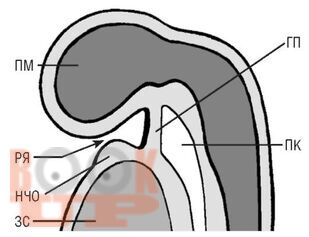

Учебное пособие предназначено для студентов стоматологического факультета медицинских вузов, включает основной теоретический материал гистологического строения органов ротовой полости в эмбриогенезе, необходимый для освоения частного раздела дисциплины - «Гистология и эмбриональное развитие органов ротовой полости». В каждой главе приведены основные морфологические характеристики эмбрионального этапа развития органов ротовой полости, механизм возможного нарушения эмбриогенеза, приводящий к врожденным аномалиям ЧЛО. Учебное пособие может быть использовано на практических занятиях, при подготовке к итоговой, промежуточной аттестации по гистологии.